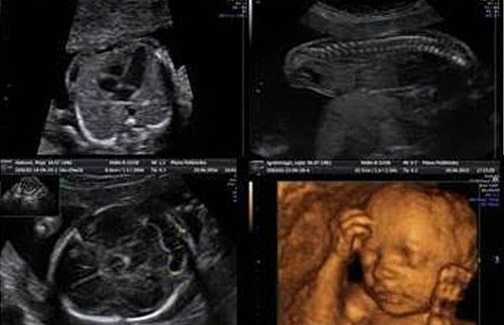

Ekspertski 4D ultrazvučni pregled od 20 do 24 nedelje trudnoće “Anatomsko-morfološki pregled sa fetalnom ehokardiografijom”

- 2D/3D/4D ANATOMSKO – MORFOLOŠKA ANALIZA

– 3D/4D mod – analiza spoljašnjeg izgleda ploda (da li postoji rascijep usne, kakva je simetrija lica, da li postoje deformiteti šake i stopala)

– analiza moždanih struktura (mali mozak, moždane komore, corpus calosum, krvni sudovi baze lobanje /3D i Power Doppler, prisustvo očnih sočiva)

– analiza trbušnih organa (uočavanje želuca i integriteta dijafragme, uočavanje mokraćne bešike i dvije arterije pupčanika, prisustvo i izgled oba bubrega)

– analiza integriteta prednjeg trbušnog zida (da li postoji defekt prednjeg trbušnog zida) - FETALNA EHOKARDIOGRAFIJA

- 3D/4D – KAKO IZGLEDA I NA KOGA LIČI?